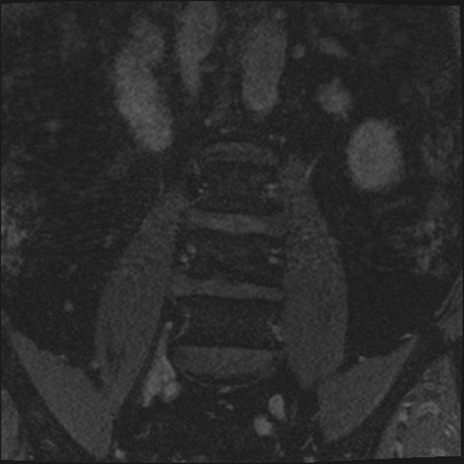

【整形】TIPS症例2 腰椎MRI 3D(冠状断像)

【症例】70歳代男性

【主訴】左下肢痛

【現病歴】2週間前くらいから腰痛、左下肢痛あり。左臀部から大腿、下腿外側のしびれが常時ある。歩行とともに同部位の痛みあり。

【身体所見】Lasegue70-/60+、Bragard-/±、PTR ±/±、ATR -/-、IP 5/5、TA 5/4、TS 5/5、EHL 右第1足趾なし/3、FHL 5/5、hypersthesia(-)、足背動脈触知良好

異常所見と診断は?